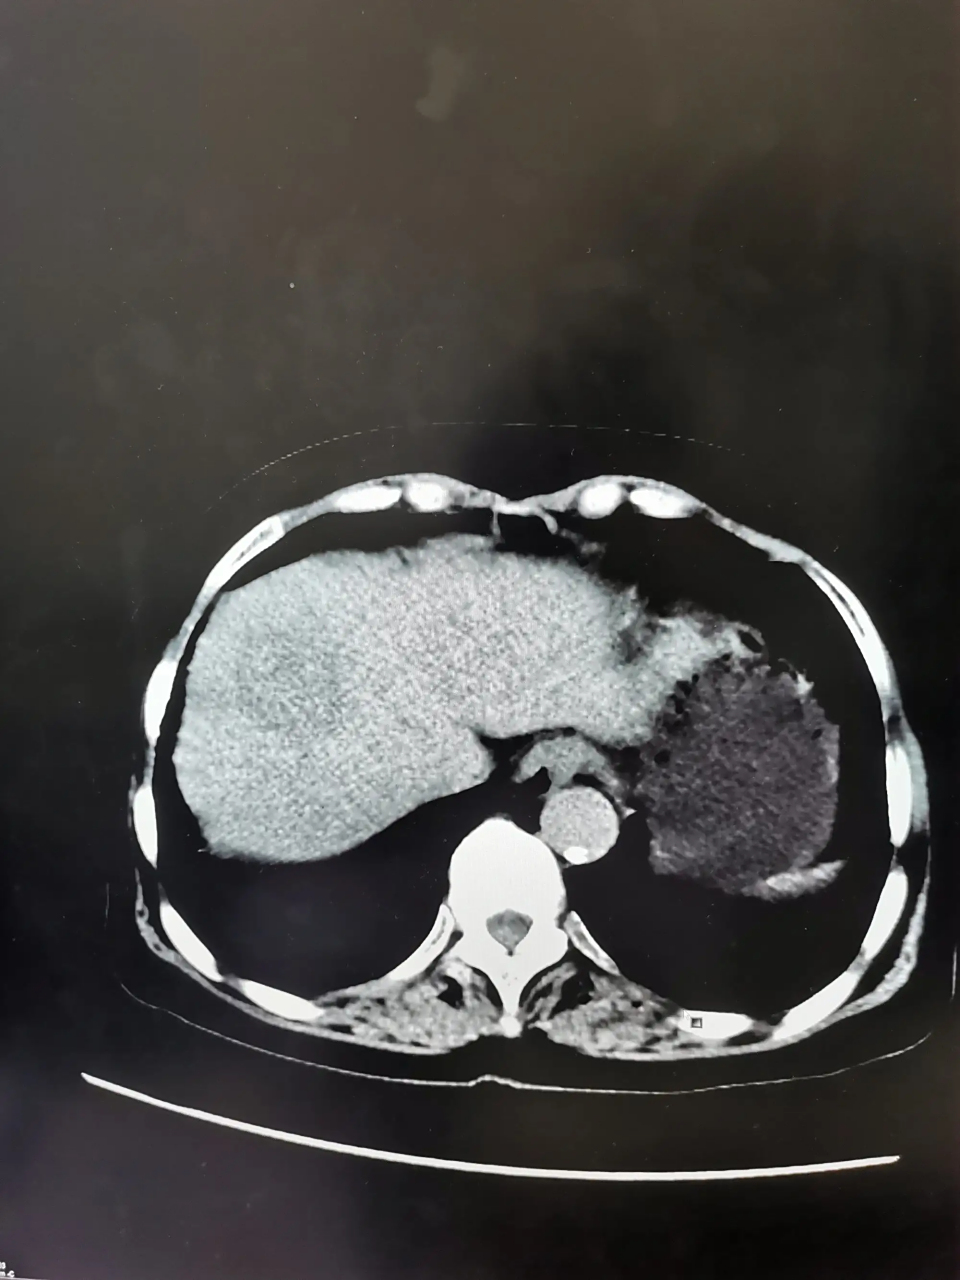

图片尺寸4032x3024

读书笔记-肝脏良性肿瘤的影像学特征